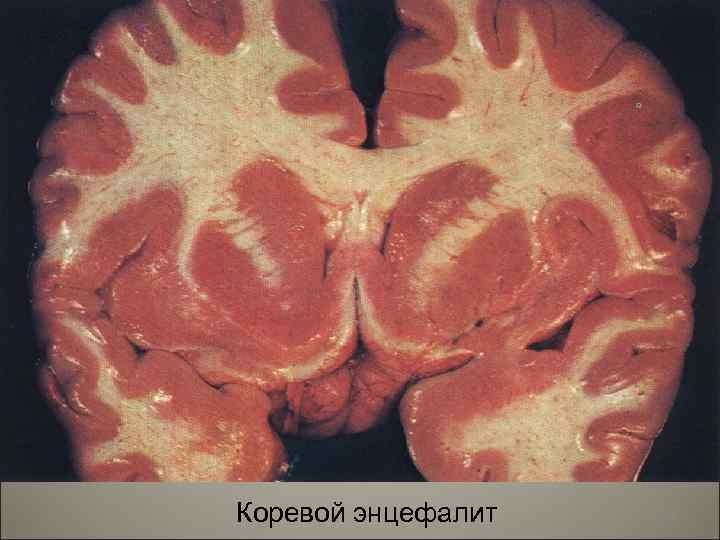

• Осложнения кори- присоединение пневмонии, отиты, мастоидиты. Поражение центральной нервной системы (энцефалит, менингоэнцефалит). Острый некротический ларингит (коревой круп), стоматиты, нома. 108

Нома 110